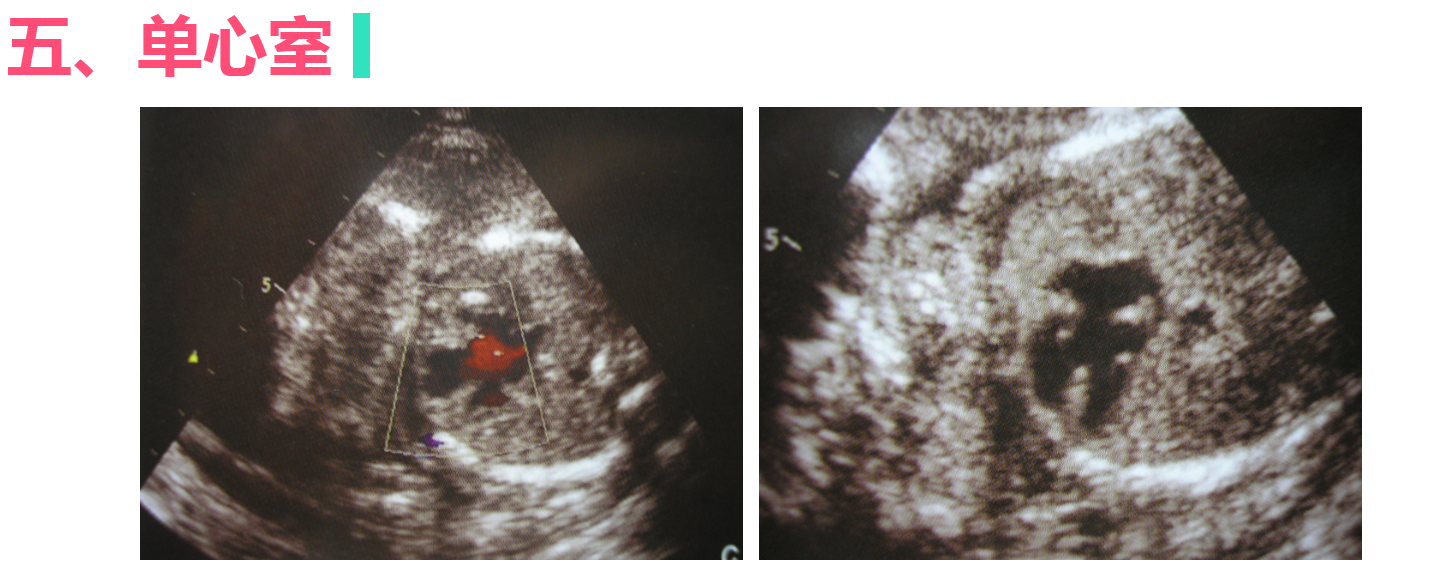

胎儿先天性畸形的超声诊断

• 4.6 胎儿先天性畸形的超声诊断